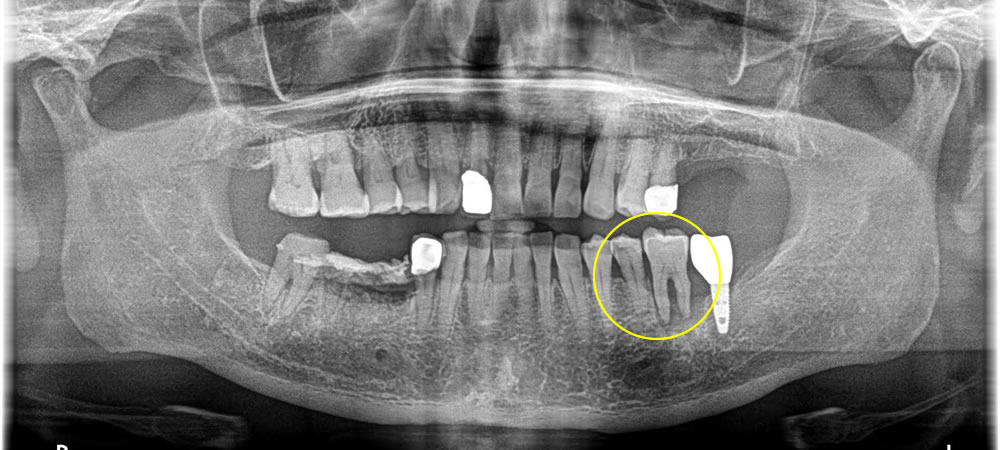

歯と歯の間の虫歯を除去しセラミックインレーで修復した症例

年齢

30代

性別

男性